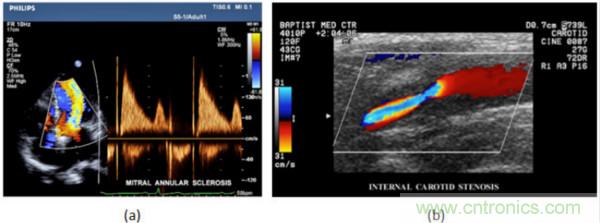

在CW和PW多普勒模式中,流信息是從一個(gè)聚焦聲束中獲得的,類似于A模式成像。在20世紀(jì)80年代,研究人員基于彩色多普勒技術(shù)完成了血流分布的二維信息可視化。彩色多普勒處理也是基于B模式/PW模式信號路徑。從感興趣區(qū)域收集多幀RF數(shù)據(jù)。由于感興趣區(qū)域中的血液流動(dòng)導(dǎo)致圖像幀之間存在數(shù)據(jù)差異。相域中的自相關(guān)和時(shí)域中的互相關(guān)兩種算法可從RF數(shù)據(jù)中提取數(shù)據(jù)方差(即血流速度和方向信息):。根據(jù)預(yù)定義的顏色漸變條相應(yīng)地映射包括速度和方向的血流信息。通常,藍(lán)色和紅色代碼分別識(shí)別朝向和遠(yuǎn)離換能器移動(dòng)的血流。當(dāng)流速增加時(shí)使用更亮的顏色,反之亦然。顏色映射的2D分布始終疊加在B模式圖像上,以實(shí)時(shí)同時(shí)顯示個(gè)體解剖結(jié)構(gòu)和血流。它對于診斷心血管疾病,如血管閉塞和心臟瓣膜反流,極其有用。典型的彩色多普勒圖像如下圖所示,(b)顯示頸動(dòng)脈狹窄引起的血流流速變化。

圖7.彩色多普勒成像:(a)以彩色多普勒和CW模式獲得的圖像(由Philips提供); (b)顯示頸動(dòng)脈狹窄的彩色多普勒(由GE提供)